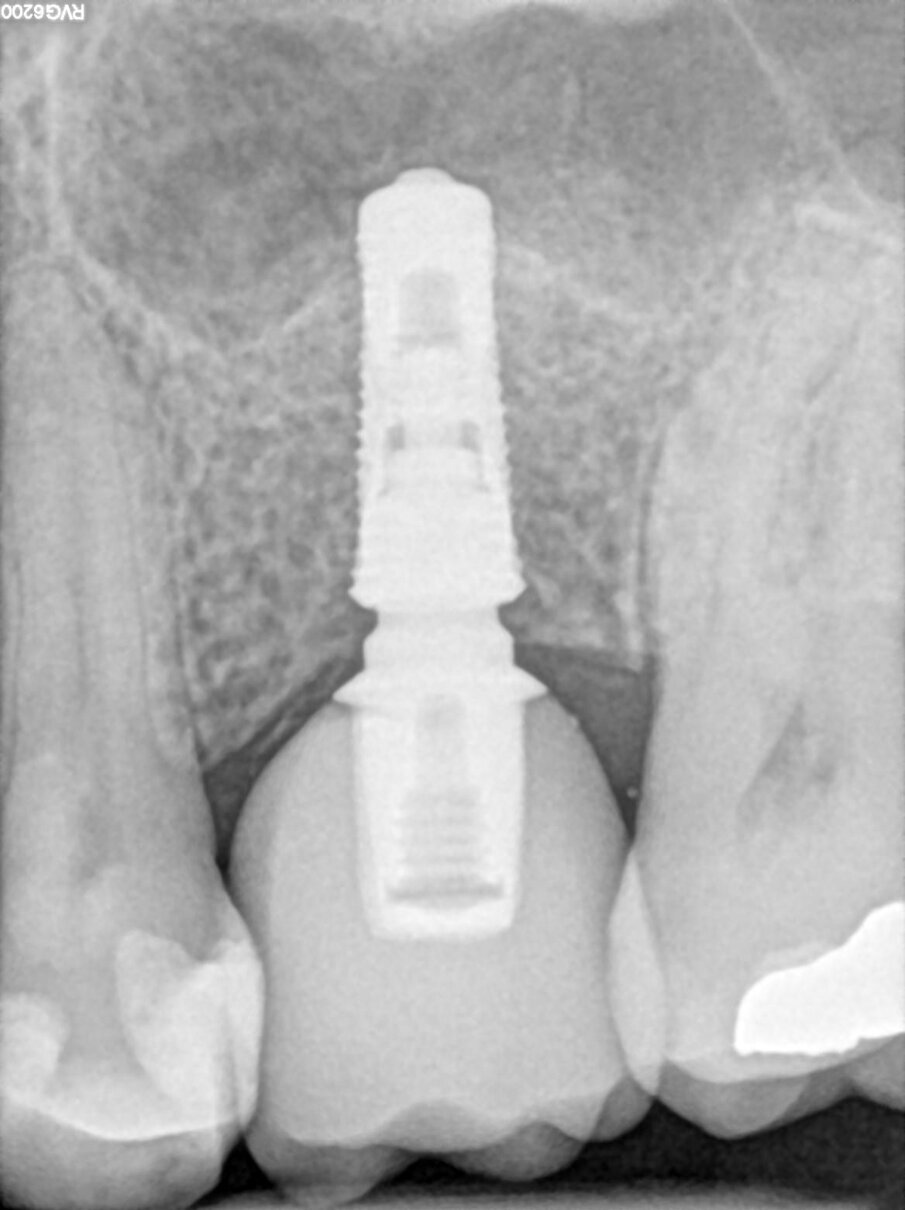

Un paziente con altezza ossea residua di 6 mm nella regione mascellare posteriore è stato sottoposto a un intervento di rialzo di seno per via transcrestale (Figg. 1, 2).

Fig. 6_Radiografia post-operatoria.

Fig. 7_Follow-up radiografico a 3 mesi.